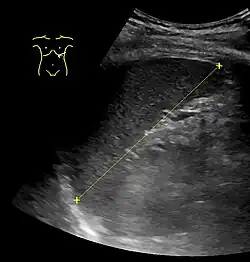

The spleen, in healthy adult humans, is approximately 7 to 14 centimetres (3 to 5+1⁄2 in) in length. It weighs between 1 oz (28 g) and 8 oz (230 g) (standard reference range),[12] correlating mainly to height, body weight and degree of acute congestion but not to sex or age.[13]

Spleen seen on abdominal ultrasonography -

Maximum length of spleen on abdominal ultrasonography -

Calculators have been developed for measurements of spleen size based on CT, US, and MRI findings.